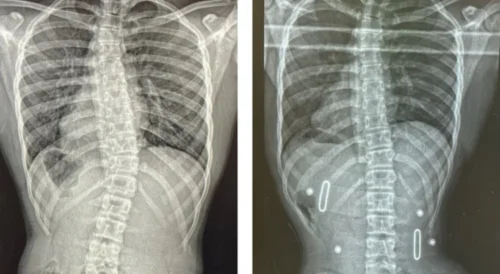

✔️ 3. استخدام حزام اعوجاج العمود الفقري

في الحالات المتوسطة:

👉 يساعد على نفليل الانحناء أثناء النمو

👉 لذلك، التدخل المبكر قد يمنع الوصول إلى الجراحة تمامًا.